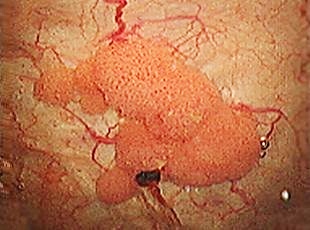

また膀胱がんに対する治療は、表在性の膀胱がんに対しては経尿道的膀胱腫瘍切除術(TUR-Bt)を行っています。

がんの浸潤度が高く、TUR-Btで不十分なときには尿路変更術を伴う膀胱全摘術を行っています。